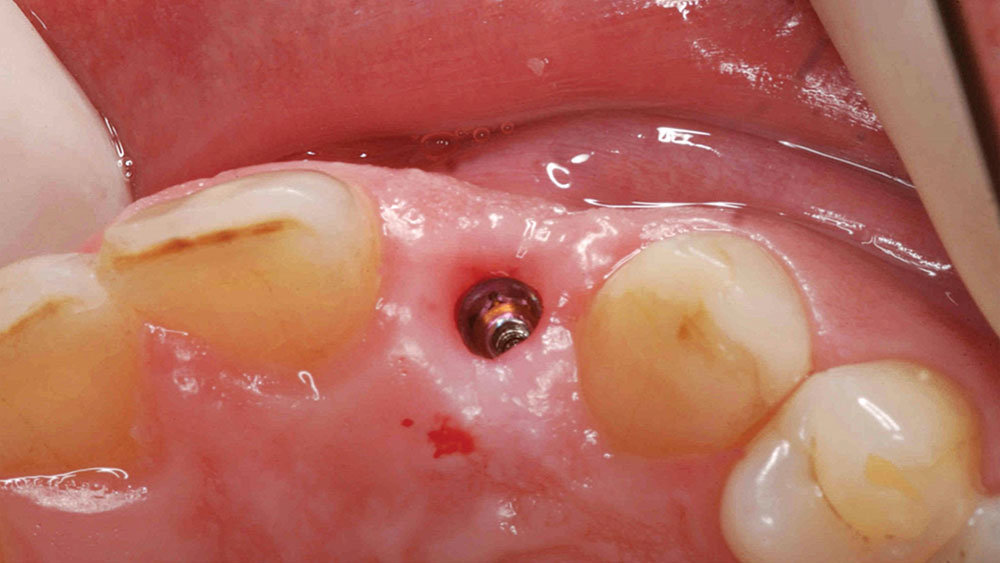

This case is an example of an ideal clinical situation for dentists who are new to placing implants in the esthetic zone. The patient requested treatment for a fractured upper lateral incisor. After extraction, grafting and healing, ample bone and soft tissue were present, and an implant was placed in optimal position for an esthetic result. The screw-retained restoration predictably restored form and function, illustrating the beautiful results that can be achieved by observing simple surgical and prosthetic guidelines.

To achieve an optimal functional and esthetic outcome, the implant must be placed correctly with regard to trajectory, adjacent vital anatomy, and buccolingual, apicocoronal and mesial-distal positioning. Situating the implant so that the edges of the osteotomy are at least 2 mm from the buccal and lingual cortical plates, 2 mm from adjacent roots, 2 mm from vital structures, and 2–3 mm below the crest of tissue will keep the implant within the envelope of acceptability. The implant trajectory should emerge lingual to the incisal edge of the planned restoration, which allows for a screw-retained crown.